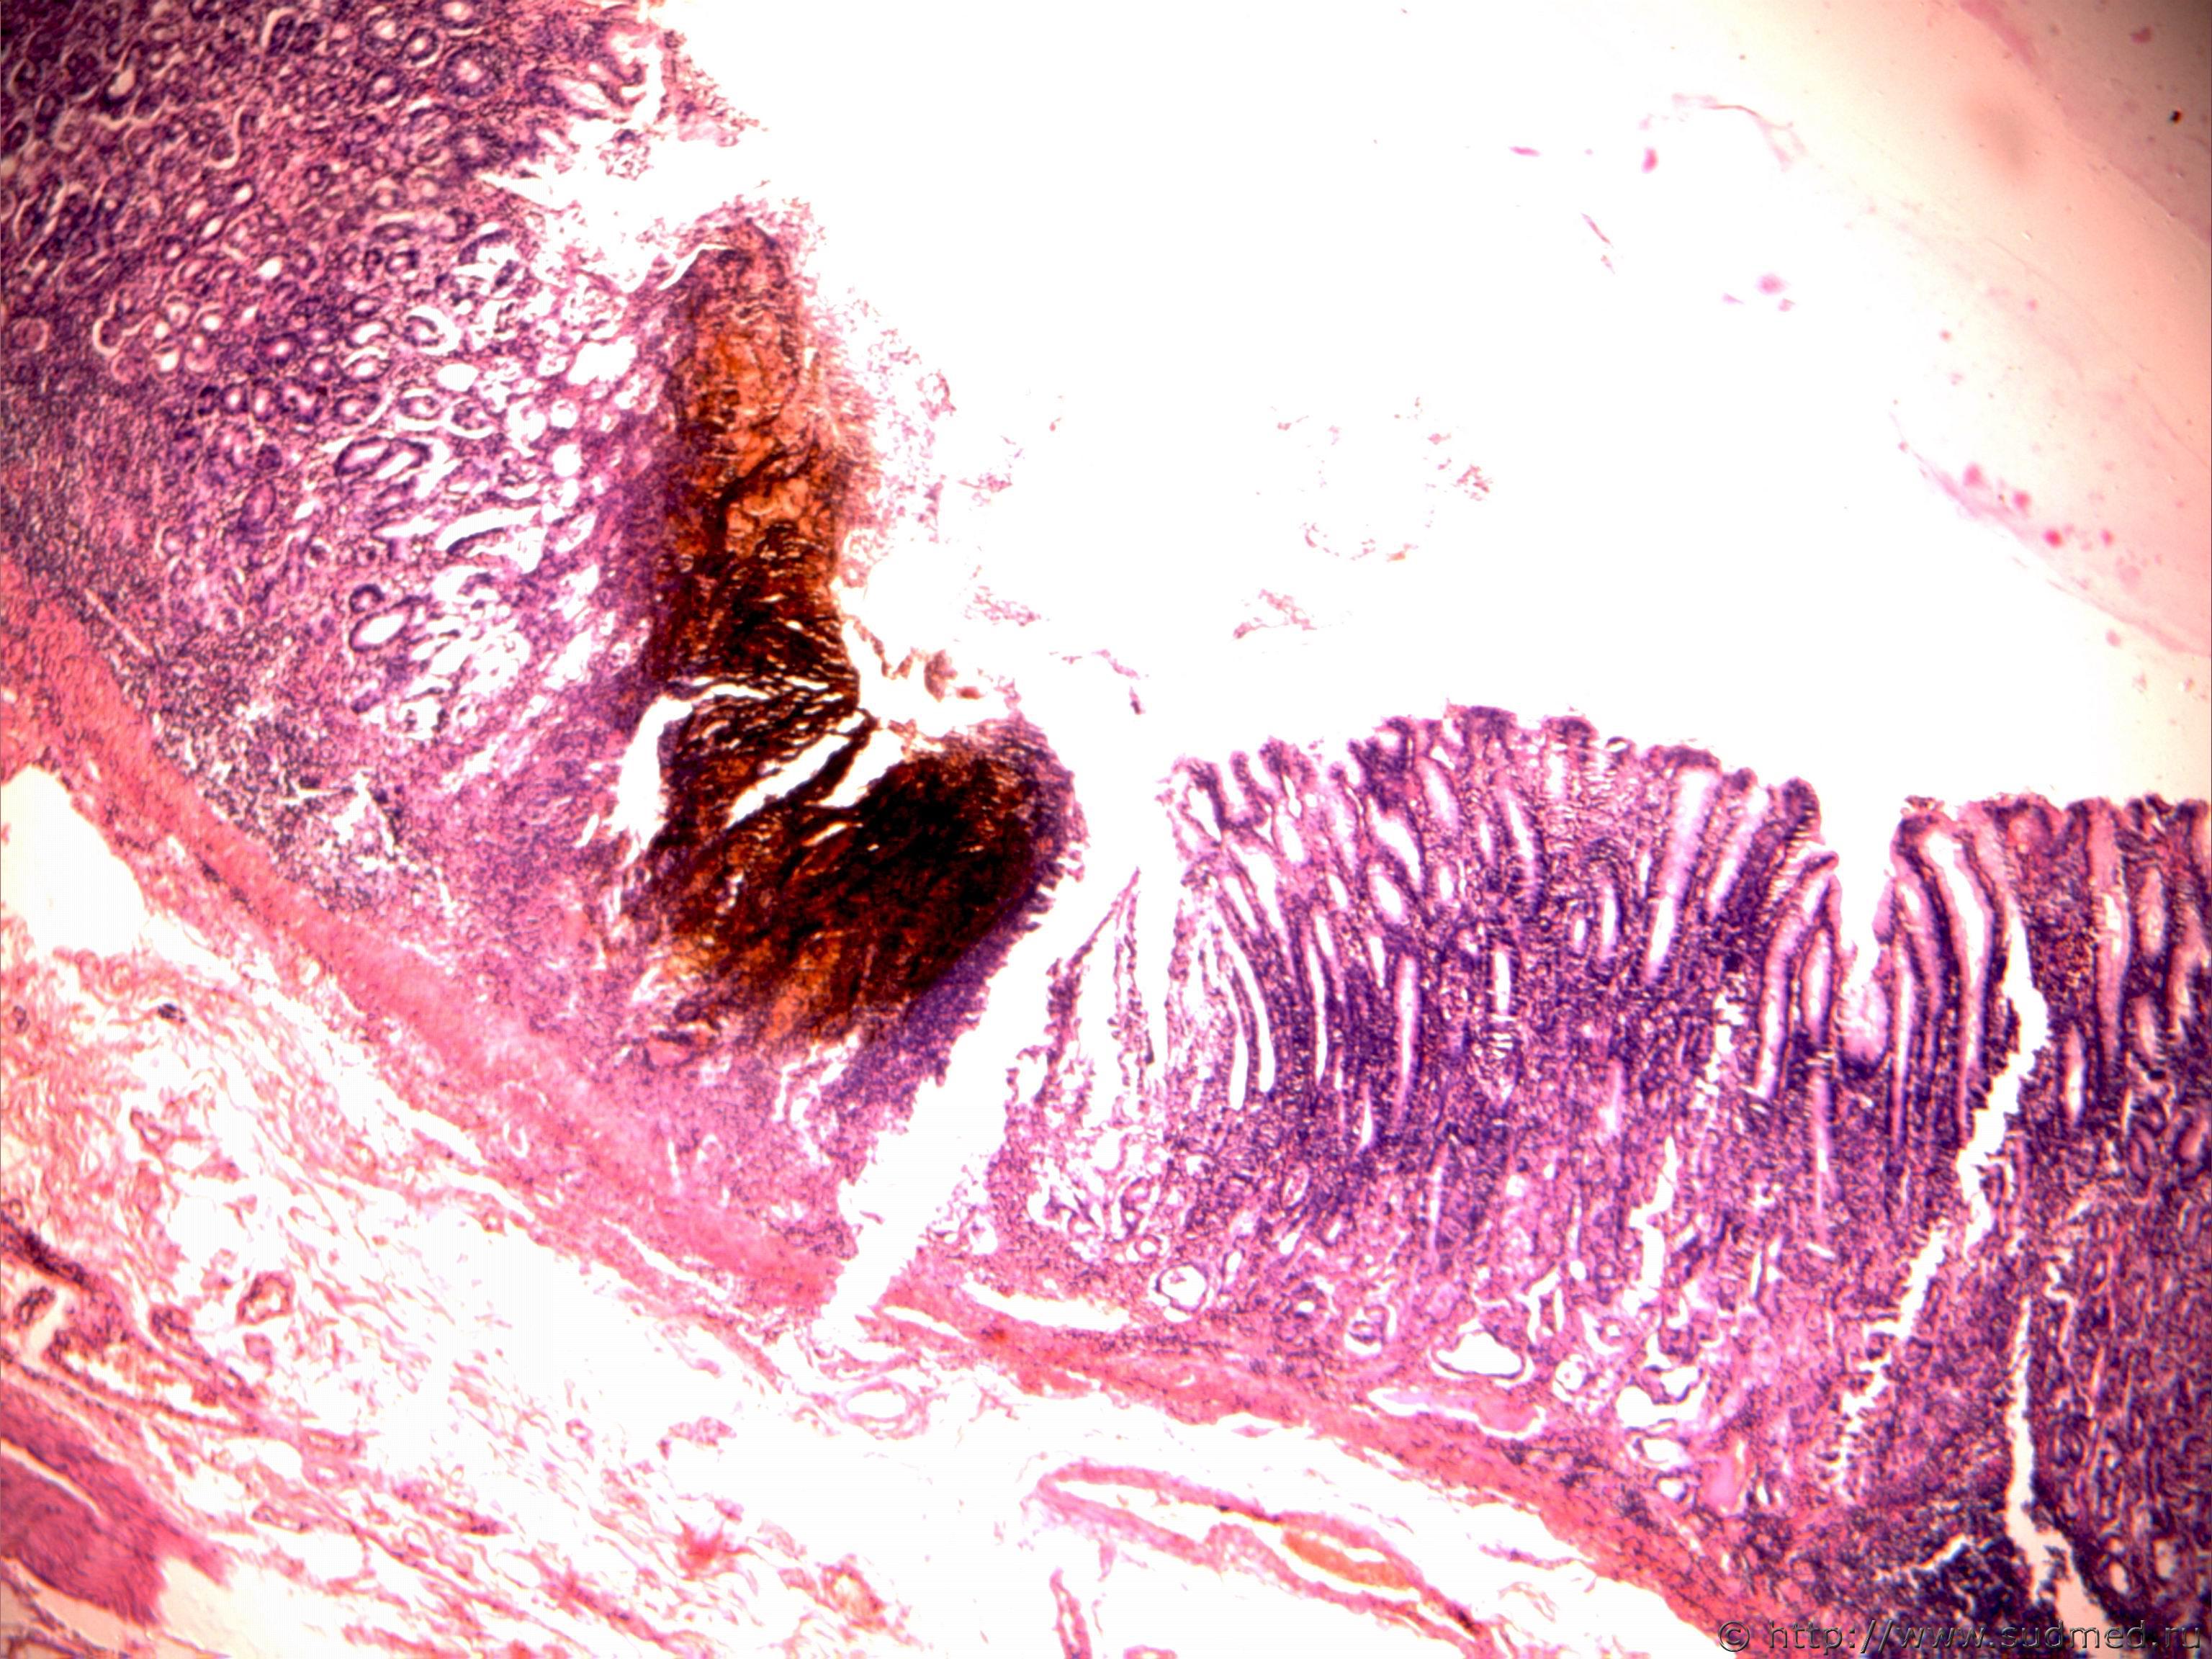

Пятна Вишневского в слизистой оболочке желудка при переохлаждении организма